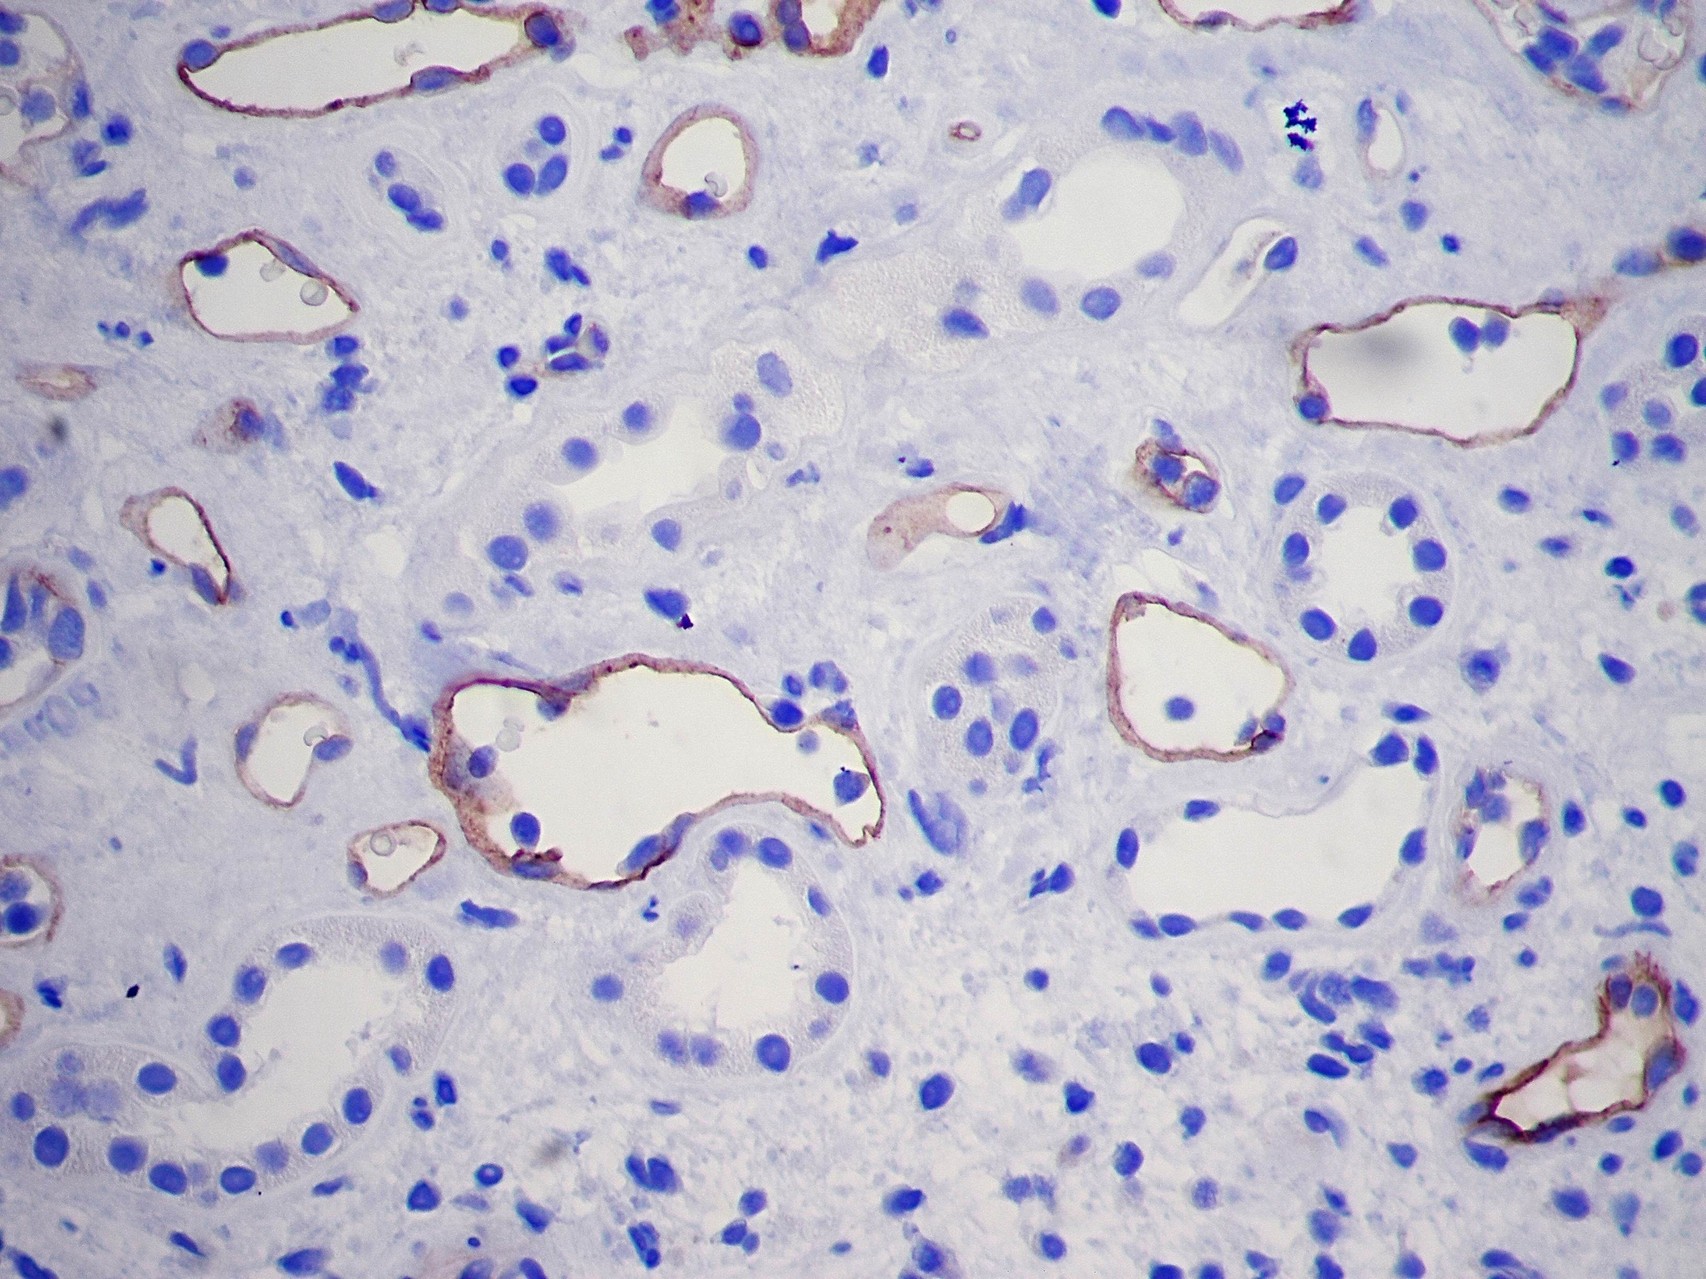

Patología Molecular

El diagnóstico sobre muestras de tejidos y líquidos corporales en plena era de la medicina del futuro, está basado en la integración de técnicas y conocimientos diferentes.

Hoy más que nunca es importante integrar una buena historia clínica con un correcto estudio de imagen y una buena morfología que además puede estar apoyada con proceso especiales complementarios relacionados con la Inmunología, Biología Molecular y Citogenética, generando así un estudio integral conocido como Patología Molecular.